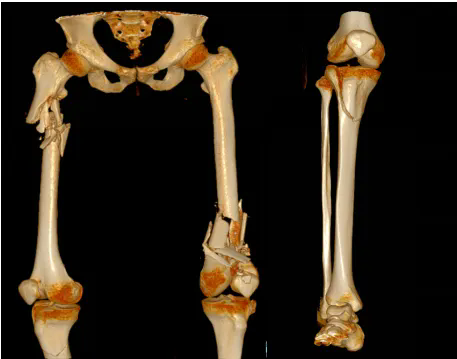

双侧股骨、右侧胫骨粉碎性骨折